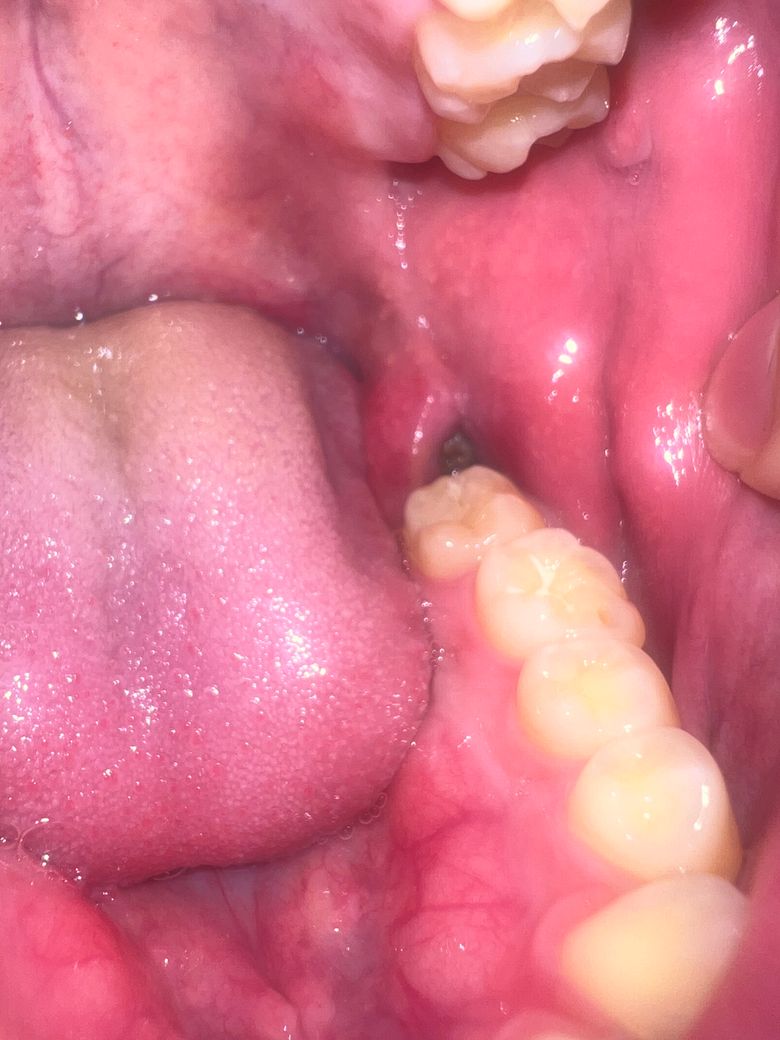

회색? 검은색으로 보이는데 양치할 때 입 헹굴 때 노란색에서 갈색 덩어리가 떨어지던데 뭔가요?? 헹구거나 해야할필요가 있을까요??

사랑니를 발치하고 해당부위에 이물질이나 가피가 형성될수 있습니다.

상피세포가 차오르면 회색빛의 막이 생깁니다. 따로 건드리지 마시고 그대로 계시면 됩니다.